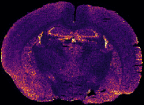

In MS imaging, data is collected from different positions in the sample, resulting in mass spectra as shown above. When the imaging analysis is complete, a single mass peak and its m/z value can be selected from the spectral data, representing a single compound detected in the sample. By plotting the intensity of this mass peak from each analysed position, MS images (heat maps) can be generated to show its relative change and thus how the compound is distributed in the sample area. For example, negative ion IR-LAAPPI MS images of a 20 μm thick slice of whole rat brain tissue measured at 70 μm spatial resolution, consisting of approximately 30,000 pixels, are shown below to illustrate how different lipid species are distributed in the brain.

| Photo | MS image | MS image | MS image |

|---|---|---|---|

![]() |

| Myelin-stained brain | GalCer(38:1) | PE(34:0) | PE-P(36:4) |

Conventional imaging techniques such as positron emission tomography, autoradiography, and immunohistochemistry, can only image a few radiotracers, radioisotopes, or antibody-labeled molecules at a time, respectively, as presented with the myelin-stained photo above. MS imaging techniques like IR-LAAPPI and IR-LAESI can image hundreds of compounds simultaneously, thereby providing a valuable tool for finding differences between sample types such as malignant and benign tumors.